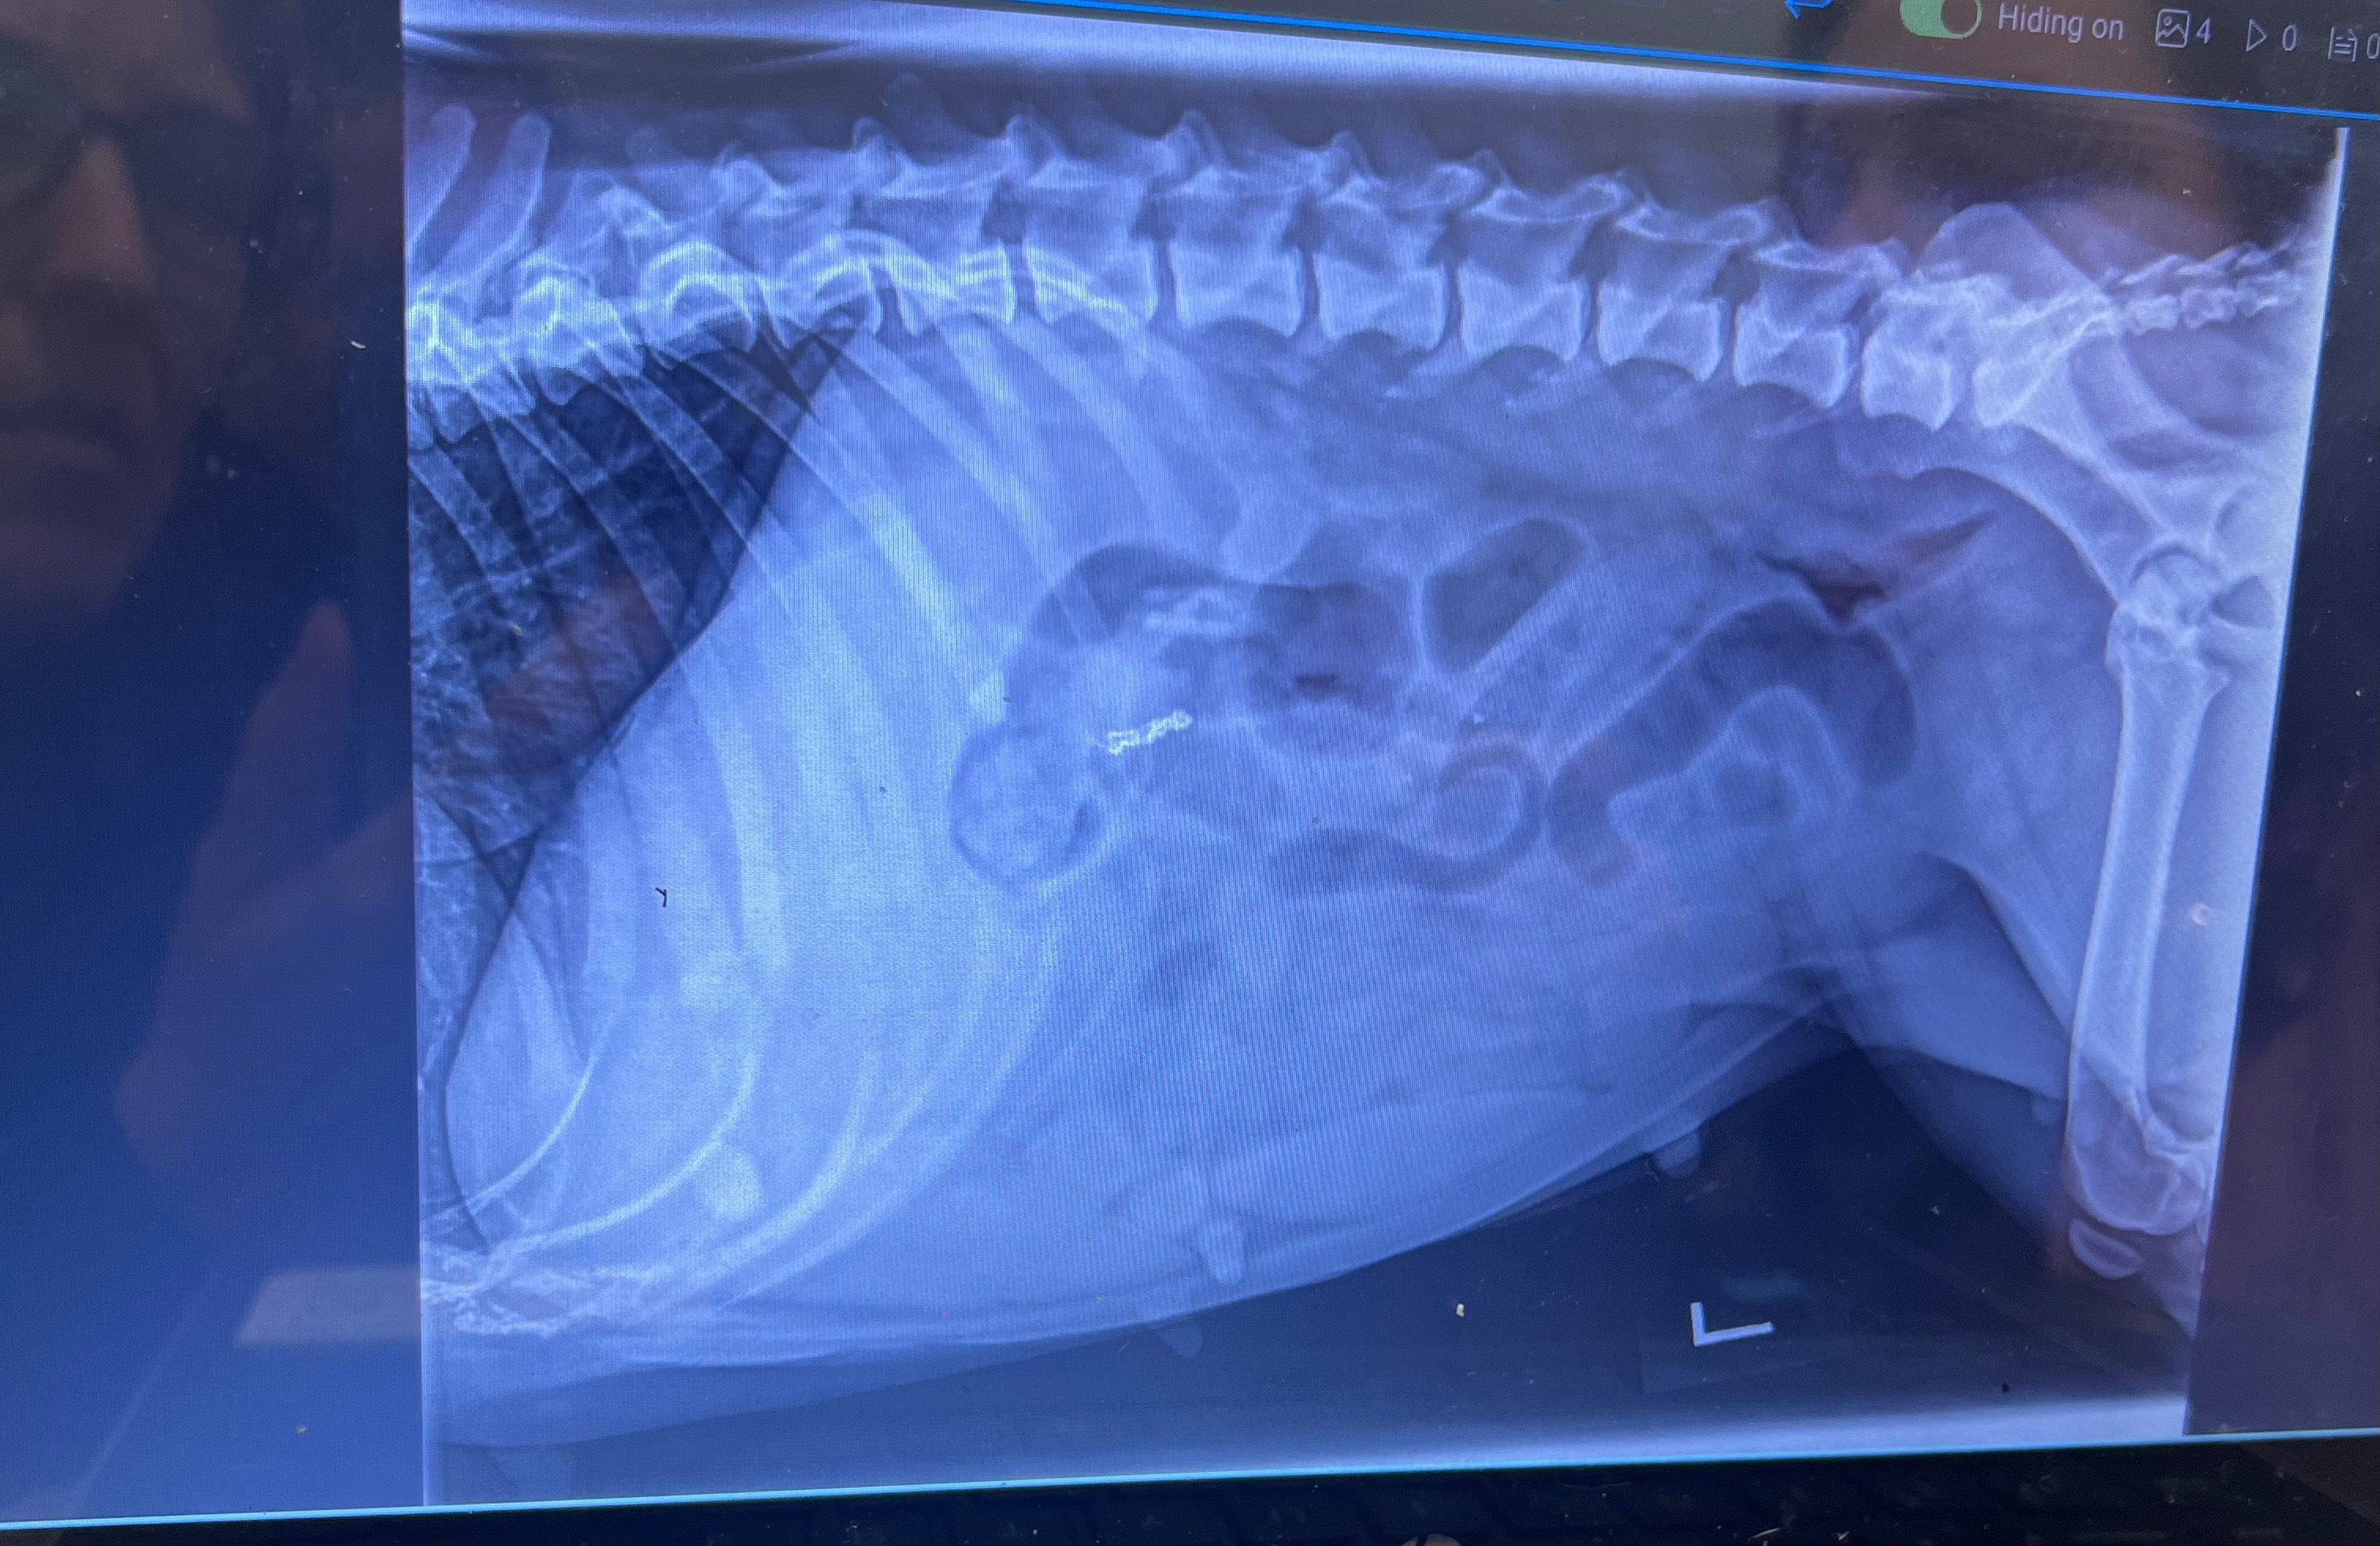

This is our baby Queen, some already know her journey and how special she is… she has recently became very ill and is now looking at needing emergency surgery to save her life ,After having x rays it shows she has a blockage in her intestines.